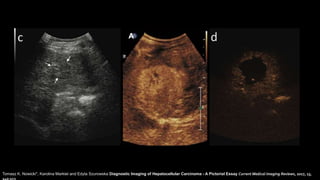

Ultrasonido

S: 33-96%

E: 90%

CEUS